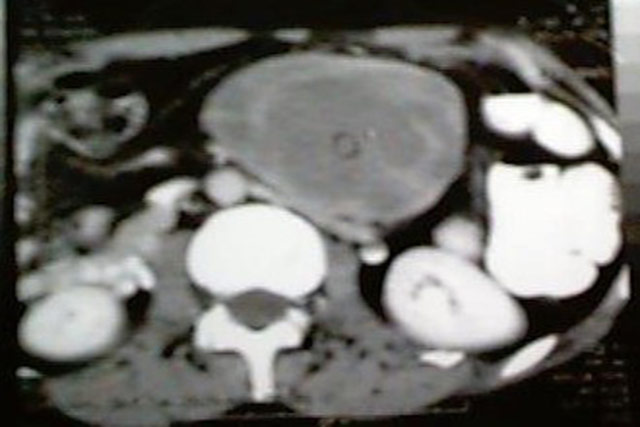

Fibrosarcoma de Mesentério